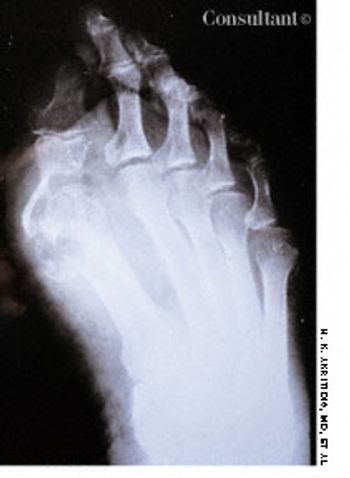

A 72-year-old woman was hospitalized after 8 years of pain and swelling of the right metatarsophalangeal joint. (In this film, the dark area over the distal joint of the large toe is an artifact.) Results of a purified protein derivative tuberculin test were positive, and a chest film revealed apical changes compatible with old tuberculosis (TB).